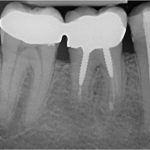

Granulomi a carico del primo molare inferiore destro.

Nei dettagli notiamo la radiografia post-operatoria dopo l’intervento di apicectomia e successivamente il controllo ad 1 anno.

Nell’ultima foto, con il controllo a 9 anni, si evidenzia la scomparsa dei granulomi grazie ad un corretto intervento di Endodonzia Chirurgica.